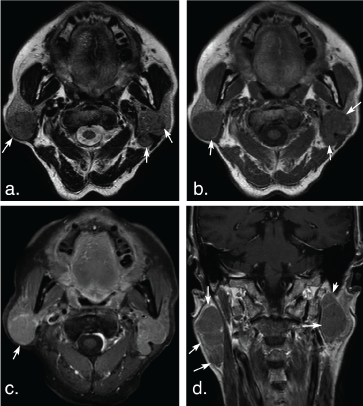

Figure 1: A 75-year-old man with basal cell adenoma in both superficial and deep lobes in the right parotid gland. Axial T2 weighted image (a) and axial T1 weighted image (b) show a well-defined, encapsulated, heterogeneous, lobulated tumor with irregular cystic area (arrowheads) and solid nodule (arrows). The solid portion of the tumor shows hypoinentse signal on T2 weighted and T1 weighted images and marked enhancement (arrow) compared with the surrounding parotid gland on axial contrast-enhanced fat-suppressed T1 weighted image (c) but mild enhancement (arrow) on coronal non-fat suppressed T1 weighted image (d) (arrows). View Figure 1

Figure 2: A 53-year-old man with basal cell adenoma in the deep lobe of the left parotid gland. Axial T2 weighted image (a) and T1 weighted image (b) shows a well-defined, ovoid solid-looking tumor (arrows). The tumor shows slight hypointense signal on T2 weighted image and T1 weighted image, marked enhancement (arrow) on axial contrast-enhanced fat-suppressed T1 weighted image (c) but mild enhancement (arrow) on coronal non-fat suppressed T1 weighted image (d). View Figure 2